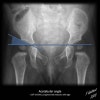

4. Pelvic development

Hip bone ossifies from 8 centres.

At birth, the three primary centers are separate.

7-8yrs, the inferior rami of the pubis and ischium are almost completely united by bone.

Acetabulum achieve radiographic closure around age of 18 Iliac crests fuse in late 20’s.

Greater trochanter fuses at around age 14.

Femoral epiphysis fuses at around 14 for girls and 16 for boys.